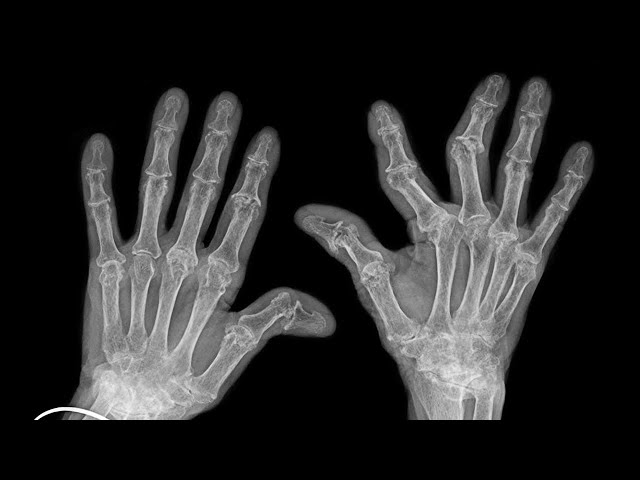

What Happens When You Crack Your Knuckles?